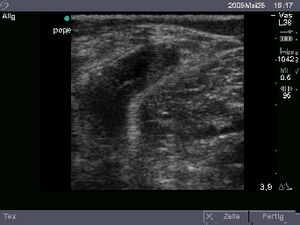

Ultraschall

In der Praxis sind 6 Farb-Ultraschallgeräte vorhanden. Hiermit können Ultraschalluntersuchungen des gesamten Bewegungsapparates, des Bauches sowie der Gefäße durchgeführt werden